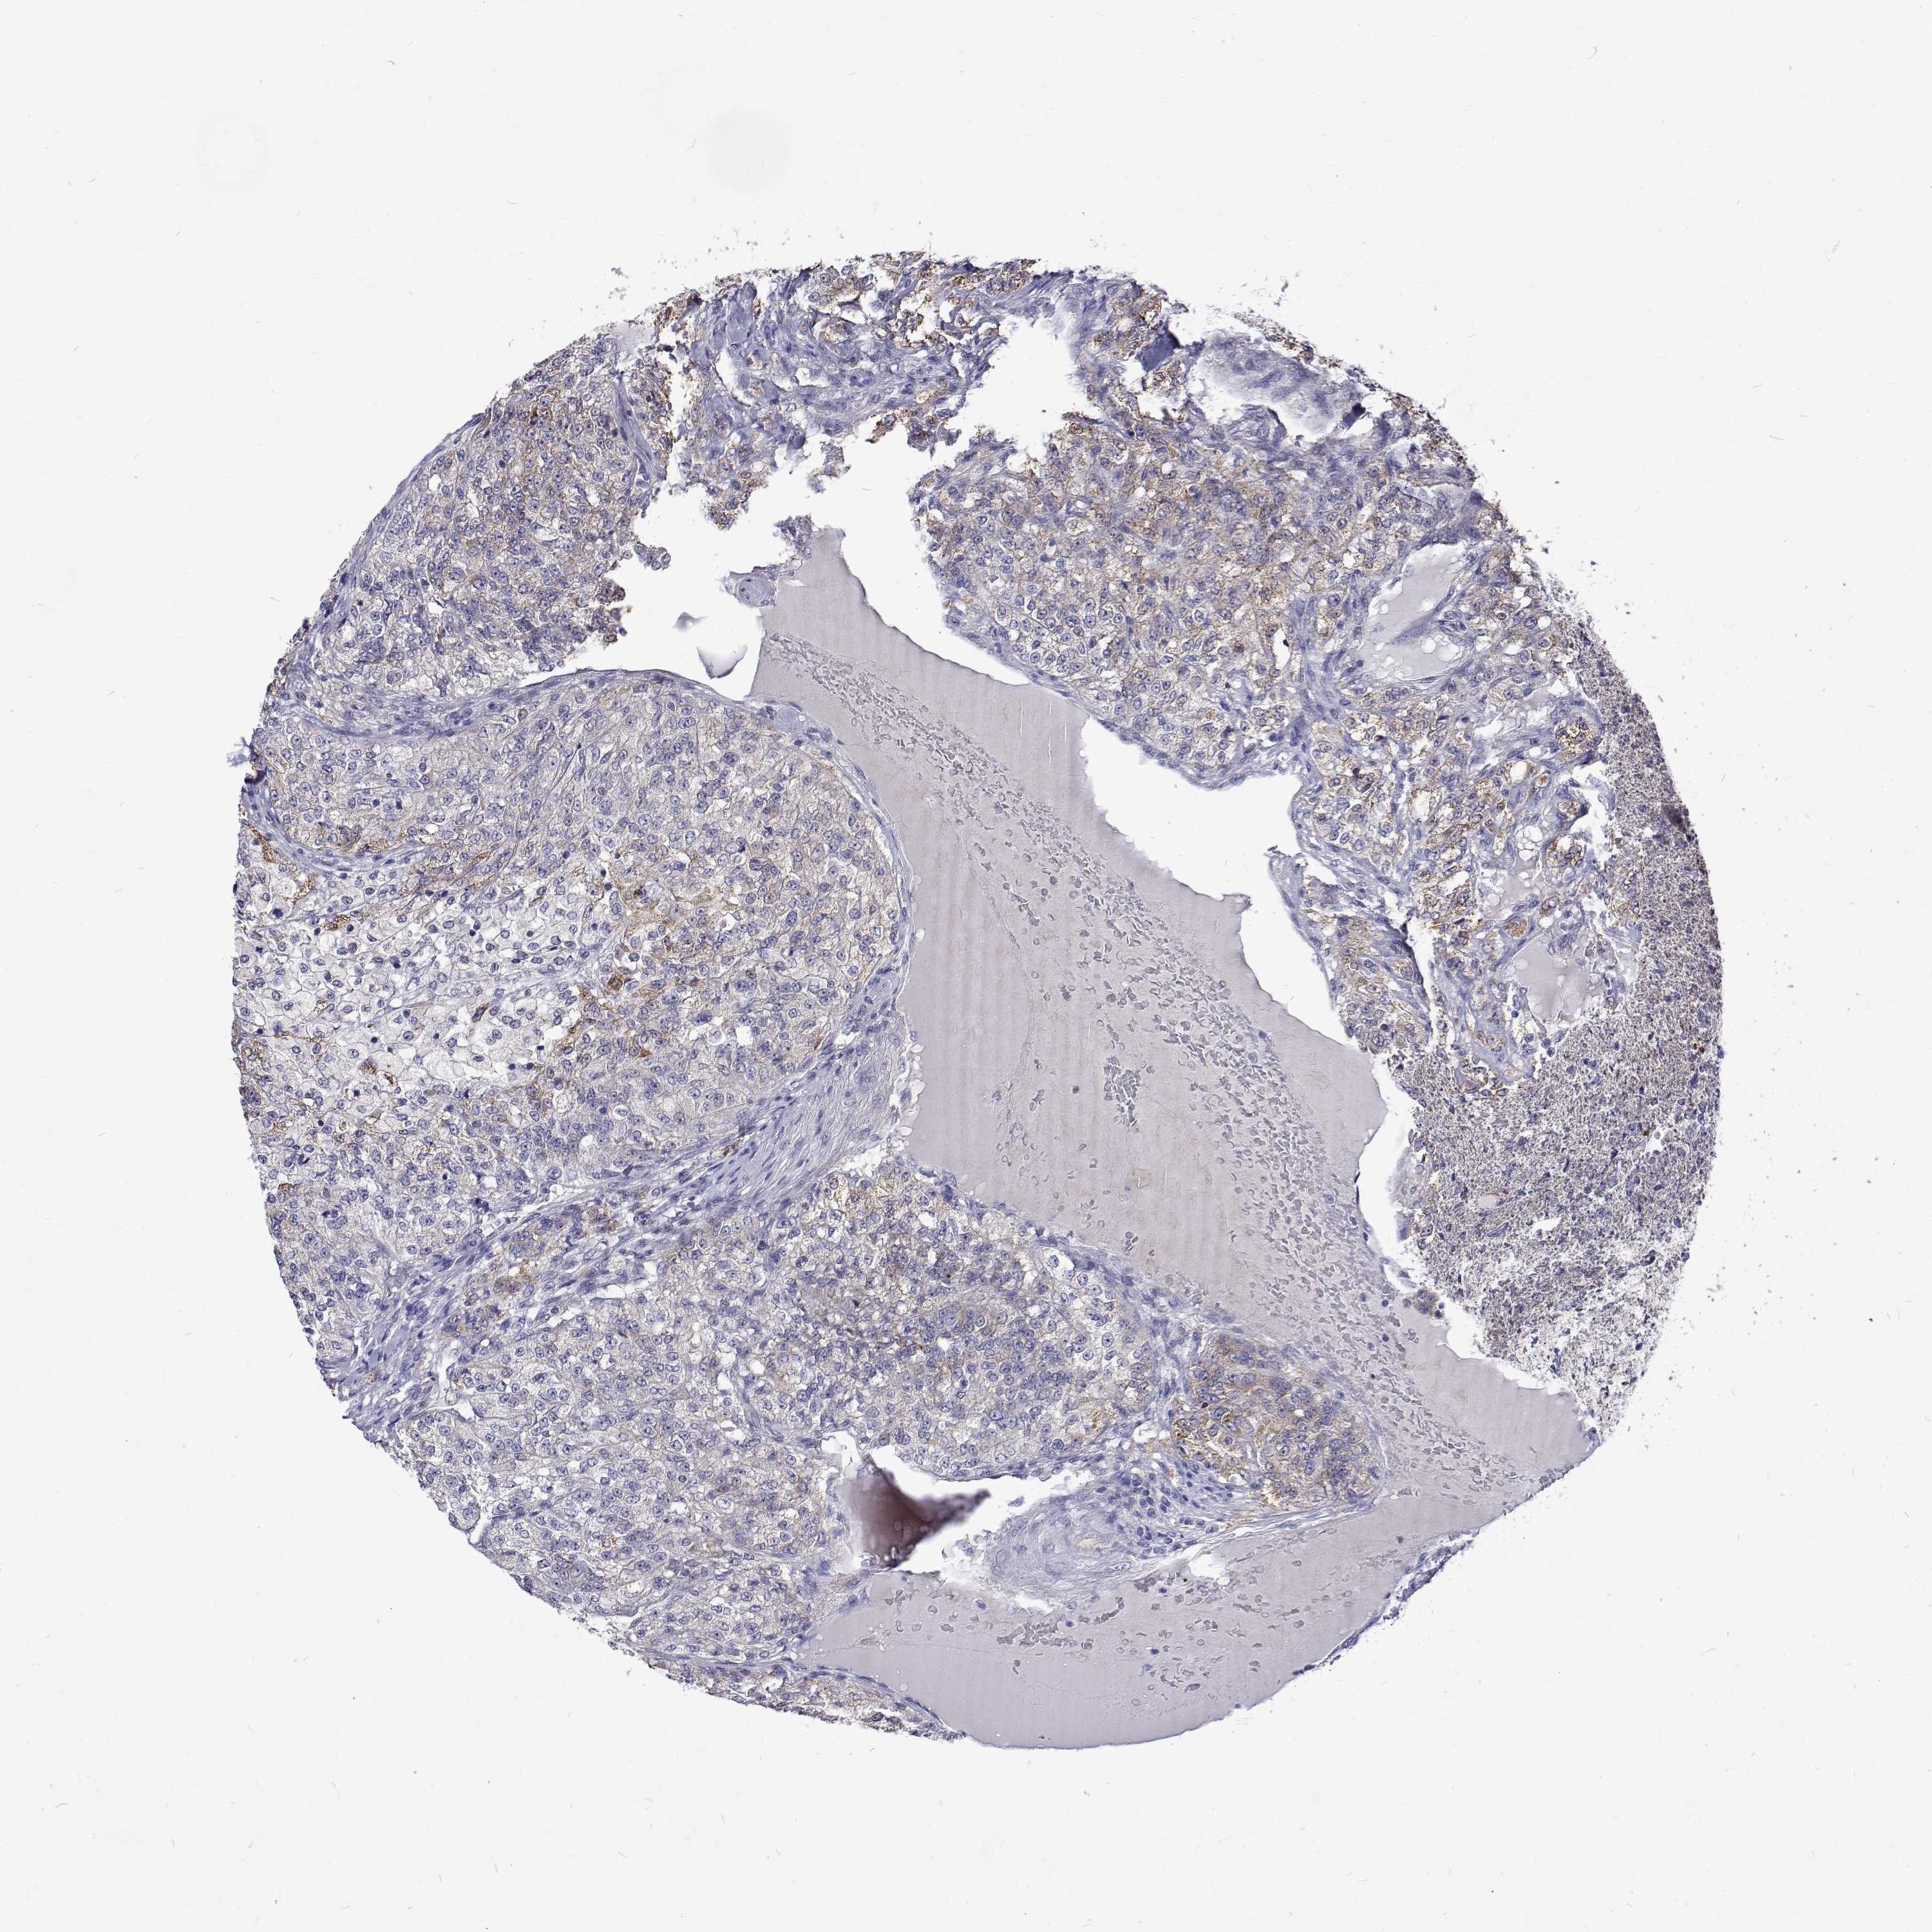

KIDNEY RENAL CLEAR CELL CARCINOMA (VALIDATION) - Interactive survival scatter ploti

The Survival Scatter plot shows the clinical status (i.e. dead or alive) for all individuals in the patient cohort, based on the same data that underlies the corresponding Kaplan-Meier plots. Patients that are alive at last time for follow-up are shown in blue and patients who have died during the study are shown in red.

The x-axis shows the expression levels (FPKM) of the investigated gene in the tumor tissue at the time of diagnosis. The y-axis shows the follow-up time after diagnosis (years). Both axes are complimented with kernel density curves demonstrating the data density over the axes. The top density plot shows the expression levels (FPKM) distribution among dead (red) and alive patients (blue). The right density plot shows the data density of the survived years of dead patients with high and low expression levels respectively, stratified using the cutoff indicated by the vertical dashed line through the Survival Scatter plot. This cutoff is automatically defined based on the FPKM cutoff that minimizes the p-score. The cutoff can be changed by dragging the vertical line or by entering a cutoff value in the square labeled "Current cut-off".

Under the Survival Scatter plot the p-score landscape (black curve; left axis) is shown together with dead median separation (red curve; right axis). Dead median separation is the difference in median mRNA expression between patients who have died with high and low expression, respectively. It is calculated as follows: median FPKM expression of dead patients with high expression - median FPKM expression of dead patients with low expression. This is intended to aid the user in visually exploring custom cutoffs and the associated p-scores and dead median separation.

Individual patient data is displayed and can be filtered by clicking on one or more of the category buttons on the top of the page. Categories describing expression level and patient information include: high, low, alive, dead, female, male and tumor stages. The scale of the x-axis can be toggled between linear and log-scale by clicking on the "x log" button. Mouse-over function shows TCGA ID, patient information and mRNA expression (FPKM) for each patient.

& Survival analysisi

Kaplan-Meier plots summarize results from analysis of correlation between mRNA expression level and patient survival. Patients were divided based on level of expression into one of the two groups "low" (under cut off) or "high" (over cut off). X-axis shows time for survival (years) and y-axis shows the probability of survival, where 1.0 corresponds to 100 percent.

PADI1 is not prognostic in Kidney Renal Clear Cell Carcinoma (validation)

Best expression cut offi

Based on the FPKM value of each gene, patients were classified into two groups and association between prognosis (survival) and gene expression (FPKM) was examined. The best expression cut-off refers the FPKM value that yields maximal difference with regard to survival between the two groups at the lowest log-rank P-value. Best expression cut-off was selected based on survival analysis .

When clicking on this number, the vertical dashed line indicating cut-off, the interactive survival plot, and the Kaplan-Meier curve will be adjusted to show results based on the best expression cut-off.

: 0.14

TCGA RNA samplesi

RNA-seq data is reported as average FPKM (number Fragments Per Kilobase of exon per Million reads), generated by the The Cancer Genome Atlas (TCGA) .

Normal distribution across the dataset is visualized with box plots, shown as median and 25th and 75th percentiles. Points are displayed as outliers if they are above or below 1.5 times the interquartile range. FPKM values of the individual samples are presented next to the box plot.

Average pTPM 3.1

Number of samples 100